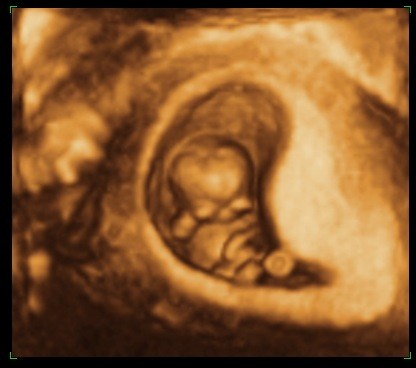

Troede ikke at den var så "levende" allerede.. Den lille fister på knap 3,4 cm sprællede helt vildt jo! Og tænk at den allerede har arme, ben, små øre, noget der ligner øjne, næse...... HELT vildt at opleve <3

Ja, det er det.. Og nu lærte jeg det lige lidt bedre tror jeg...: 4D bruger de til at se bevægelserne.

Og vi fik så både s/h, 3D og 4D